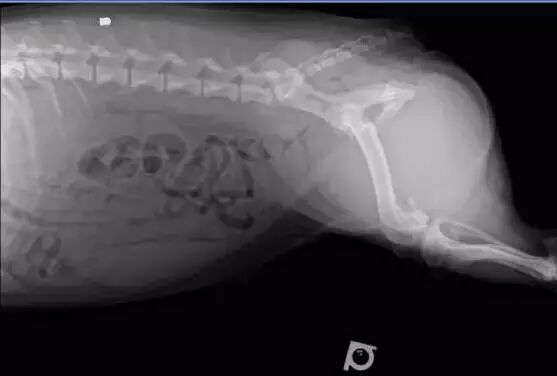

当然你可以说这是一般动物的屁股,不是柯基的呀——那我们来看两张柯基的X光照片吧!

柯基屁股的X光片。图片:mycorgi.com

我知道你可能没看懂,别着急,X光片很容易看的!在X光片中,密度越高的地方颜色越浅,譬如说骨头就接近雪白;而密度越低的区域颜色越深,空气在X光片中应该是黑色的。然后,让我们来找一找,柯基的屁股里有大量深色区域吗?并没有!